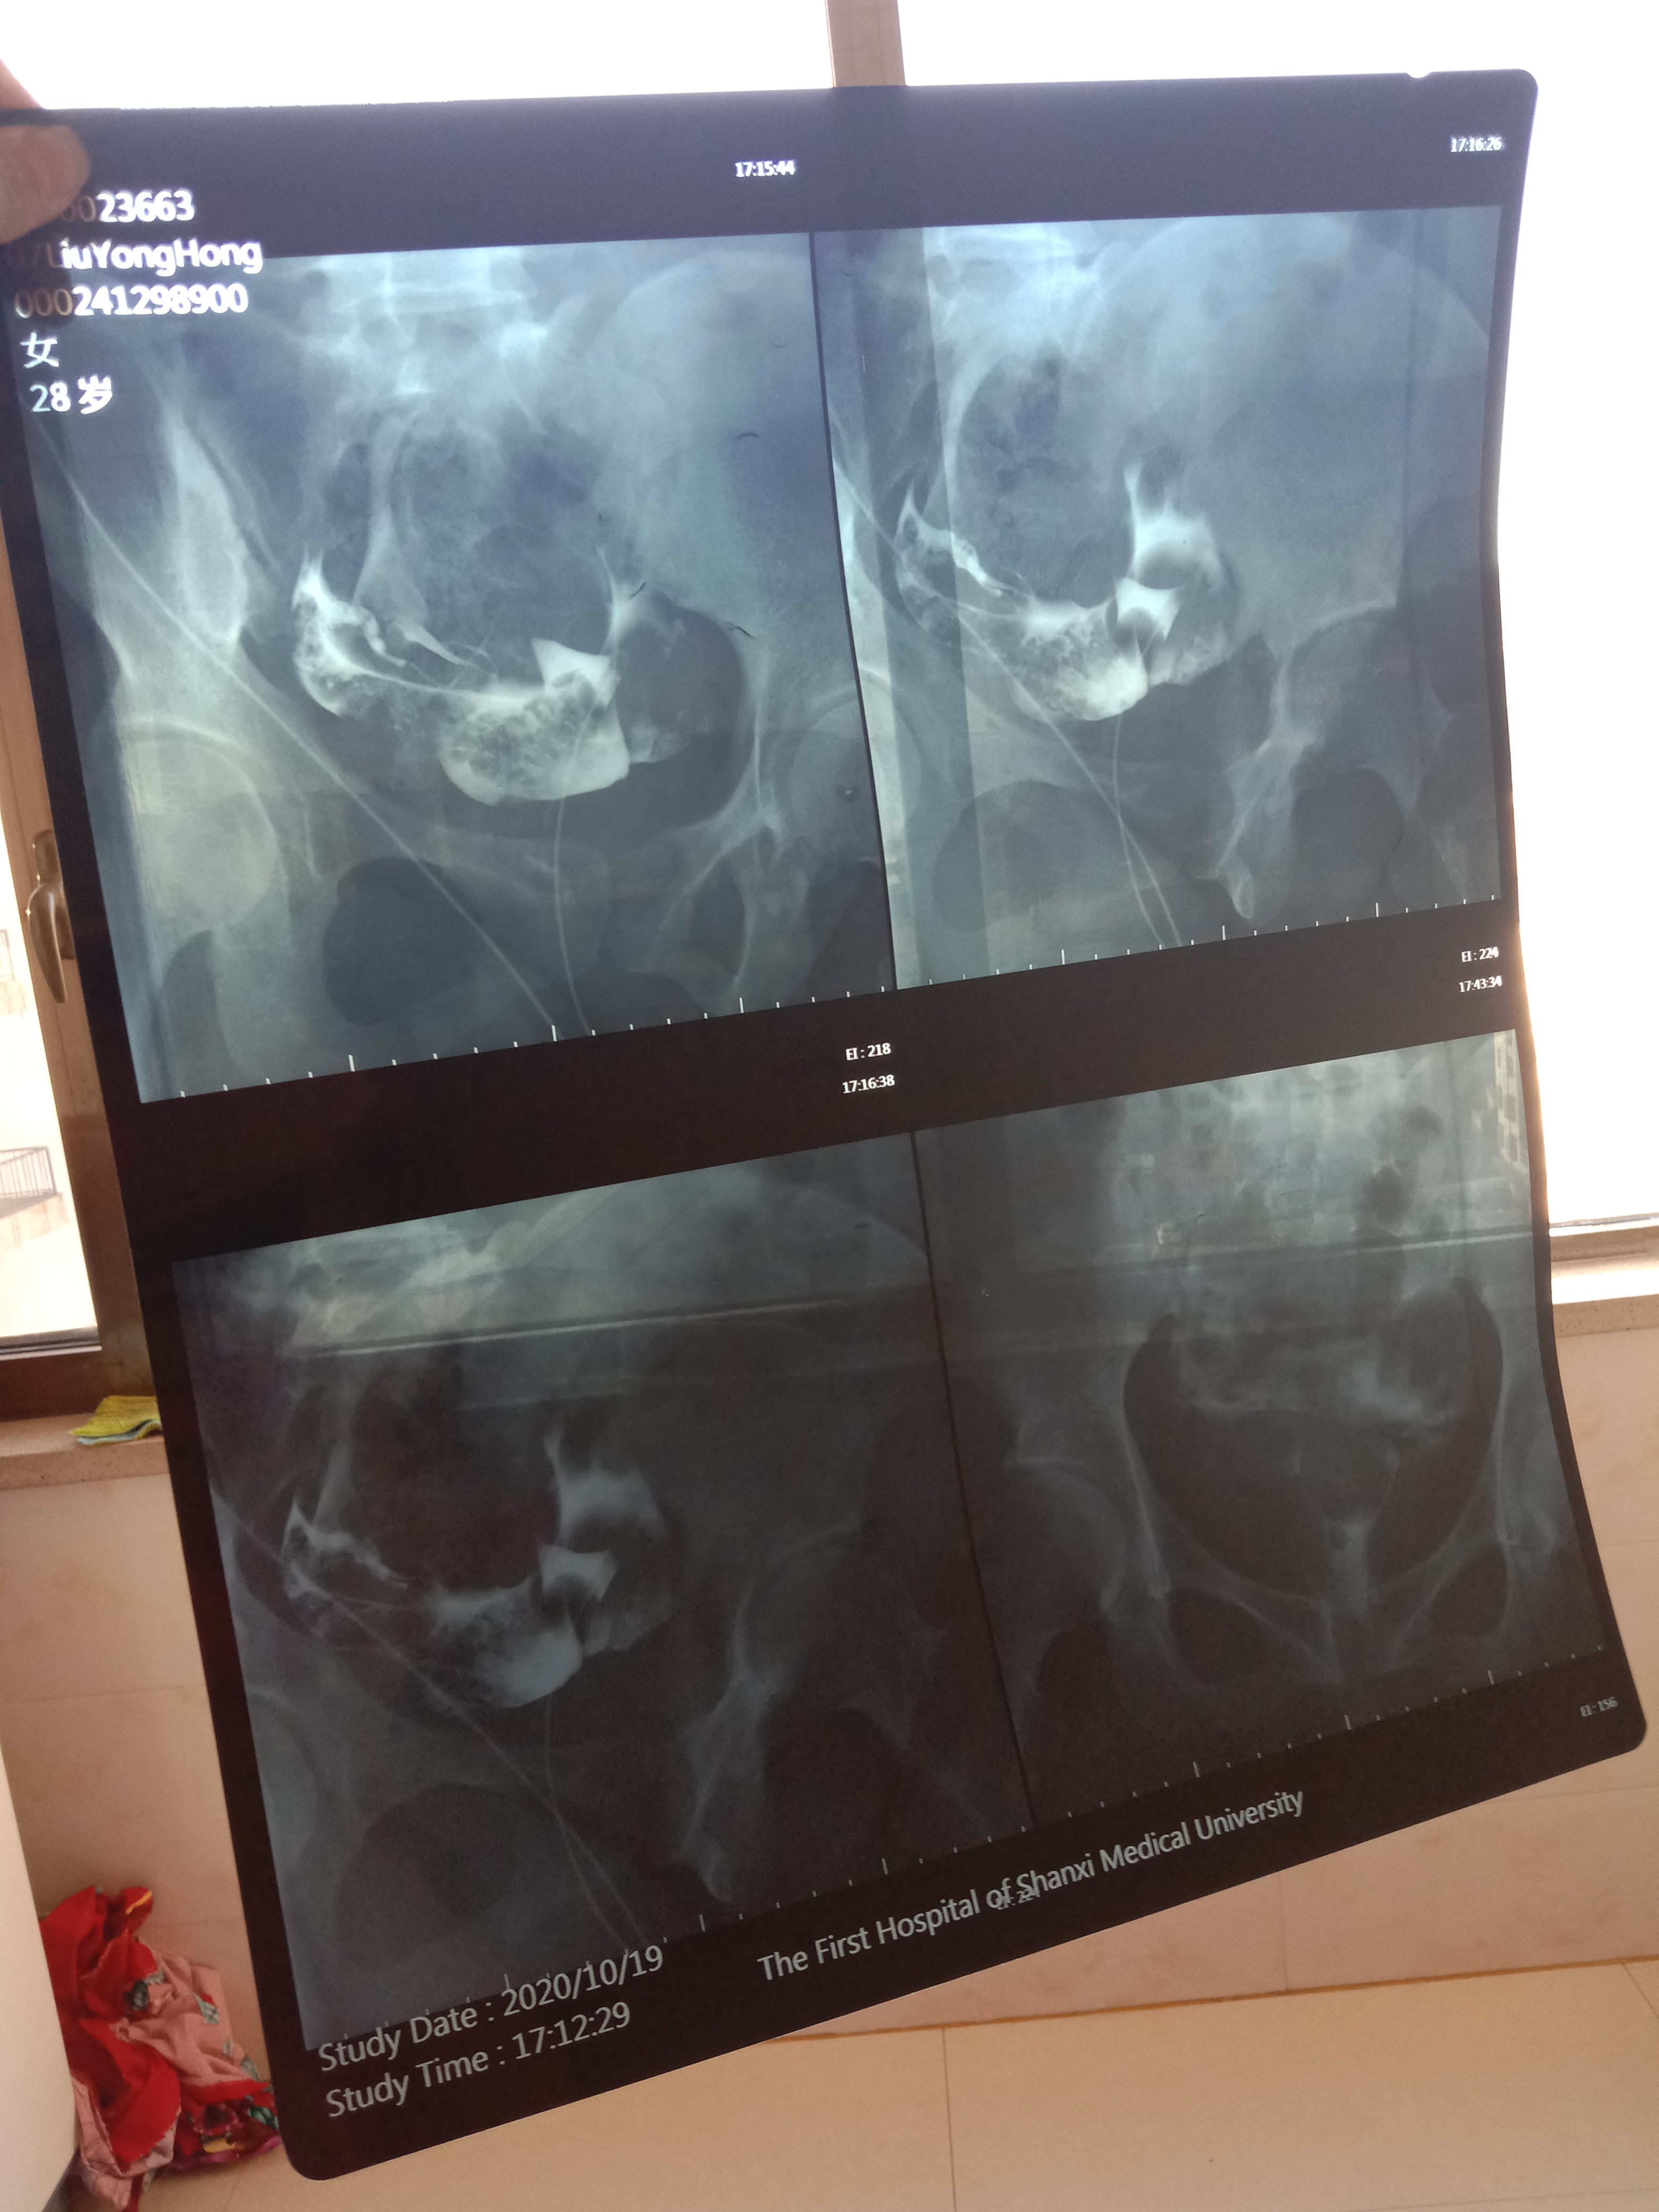

做完输卵管造影第六天了小腹还是感觉沉甸甸的如

可以热敷腹部,如果有发热,腹痛加剧,白带量多,有异味,随时就医